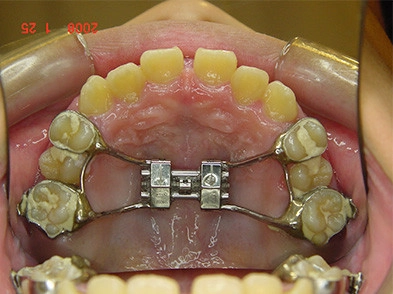

使用 RME 上顎快速擴大器 ,配合頭帽 蒸氣鼻子呼吸訓練療法

戽斗矯正案例-4